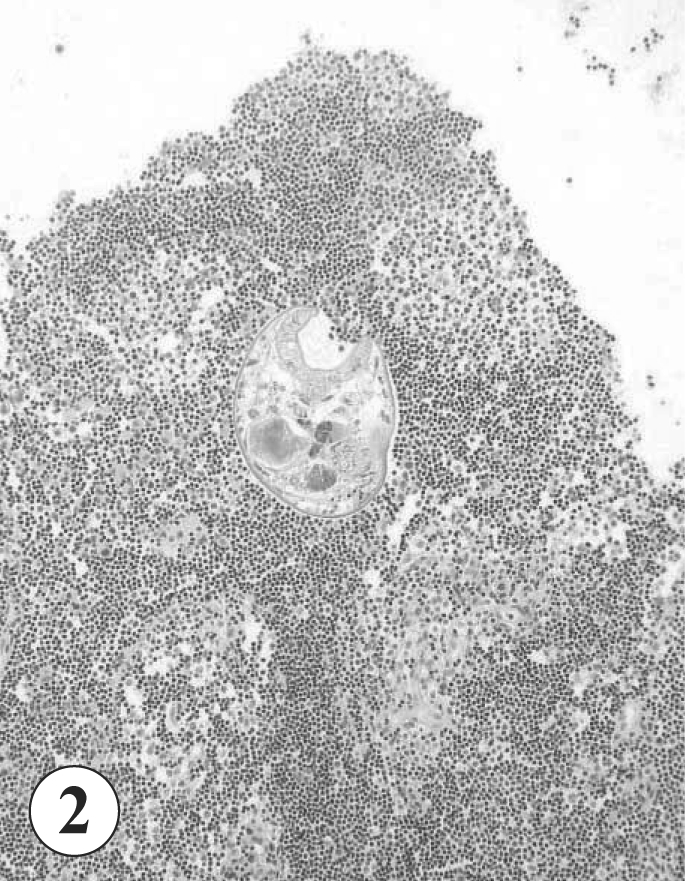

G. seoi was found in sectioned lymphoid tissue of the colonic wall (

Figs. 2-

Fig. 2Section of the lymphoid tissue of the colonic wall. A worm is vertically sectioned, its large oral sucker and internal structures are shown. H-E stain. x 40.